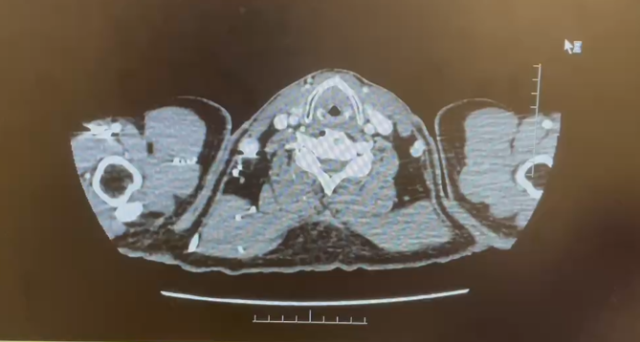

2024.1检查报告

CT 检查报告

1.左肺动脉主干及分支、右下肺动脉分支多发肺栓塞;

2.下腔静脉、右肾静脉及其属支、左肾静脉及左侧髂总静脉多发血检形成,请结合临床。

3.双肺散在炎症,双侧胸膜增厚;

4.右肾大片状低强化灶,请结合临床。

日期:2024.1.10